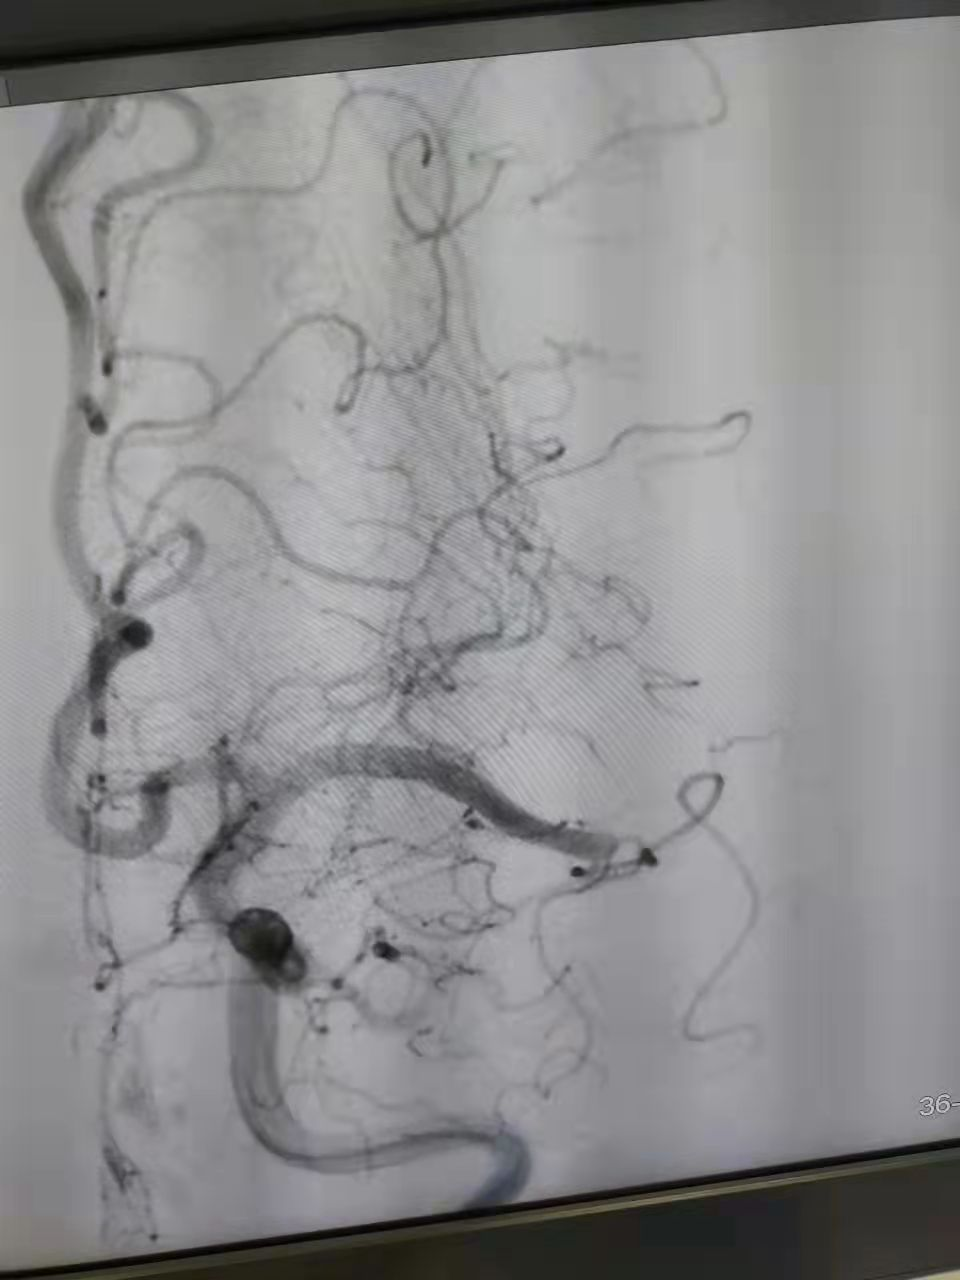

术中取出的血栓

神经内科胡华林主任及其介入团队快速制定手术方案,通过动脉抽吸血栓,再配合血管内取栓支架,1小时内快速取出了堵塞血管的血栓,陈阿姨闭塞的左侧大脑中动脉成功恢复了血流再通。手术非常顺利,陈阿姨术后言语恢复清晰,能够自由下床活动。住院3天后,省人民医院帮扶专家、心血管病专家、县人医副院长林吉进会诊,林吉进副院长针对陈阿姨心脏基础疾病及时调整用药,并叮嘱规律服药和返院复查等相关事宜,术后两周后陈阿姨顺利出院。